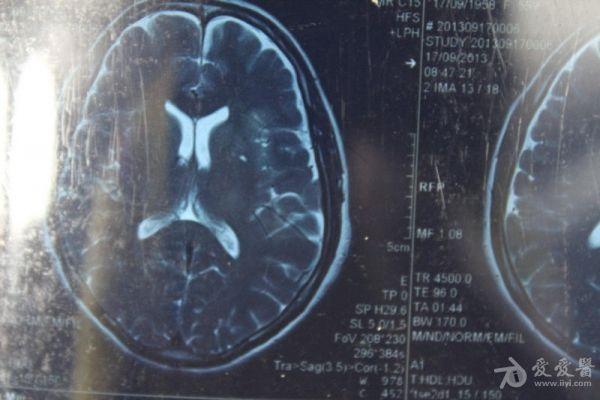

脑部占位病变CT,MRI图片,请帮忙诊断

最近感图样,无其它脑病病史

考虑脑膜瘤!!

磁共振没有平扫,增强矢状位没找到病灶。像脑膜瘤。

图片不是很清楚,应该是脑膜瘤!